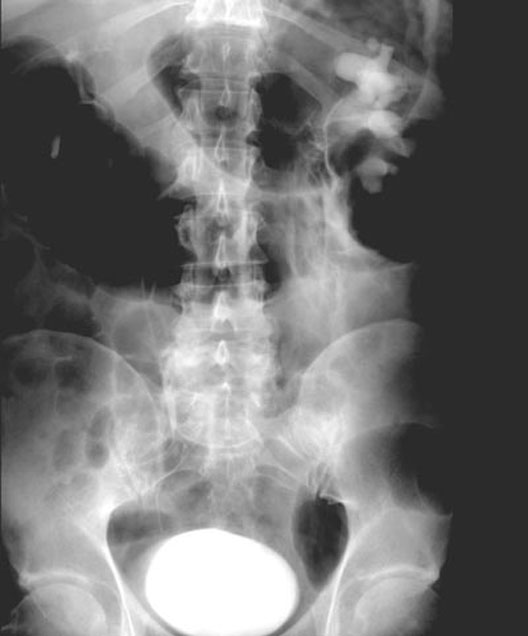

Ureteric Obstruction

*Right ureter does not show up with contrast material due to an obstruction.